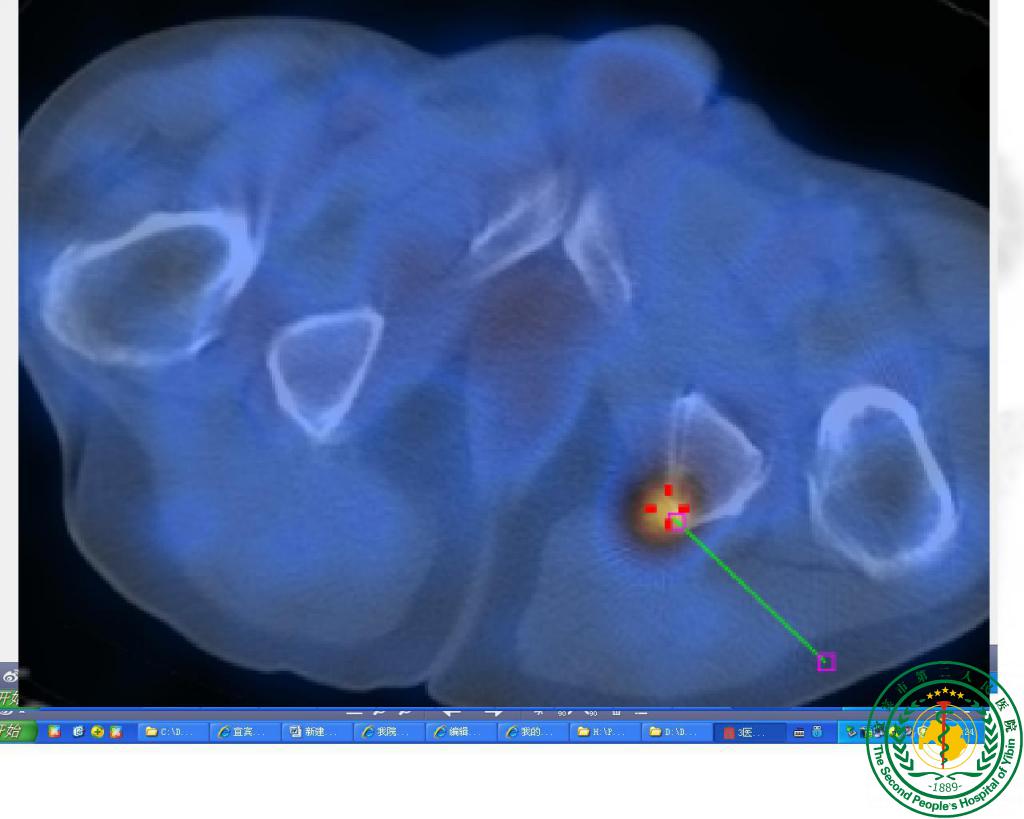

“鹰眼”派特CT确诊疑难“肺结节”一例

宜宾市第二人民医院 图文